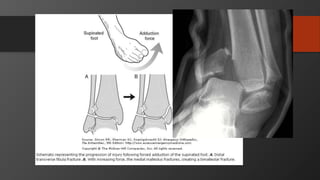

Ankle Fractures

Imaging

• AP, Lateral

• Mortise view

• CT scan

• Especially posterior malleolus

Initial treatment- reduce dislocations